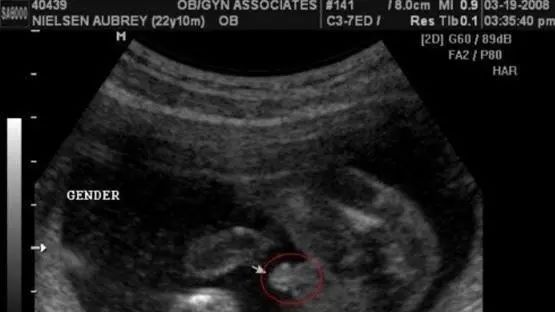

男宝宝B超图

“凸出的东西”是他的标记:你们看到圆圆的是DANDAN,如果看到圆圆的加小肠的就是全部JJ